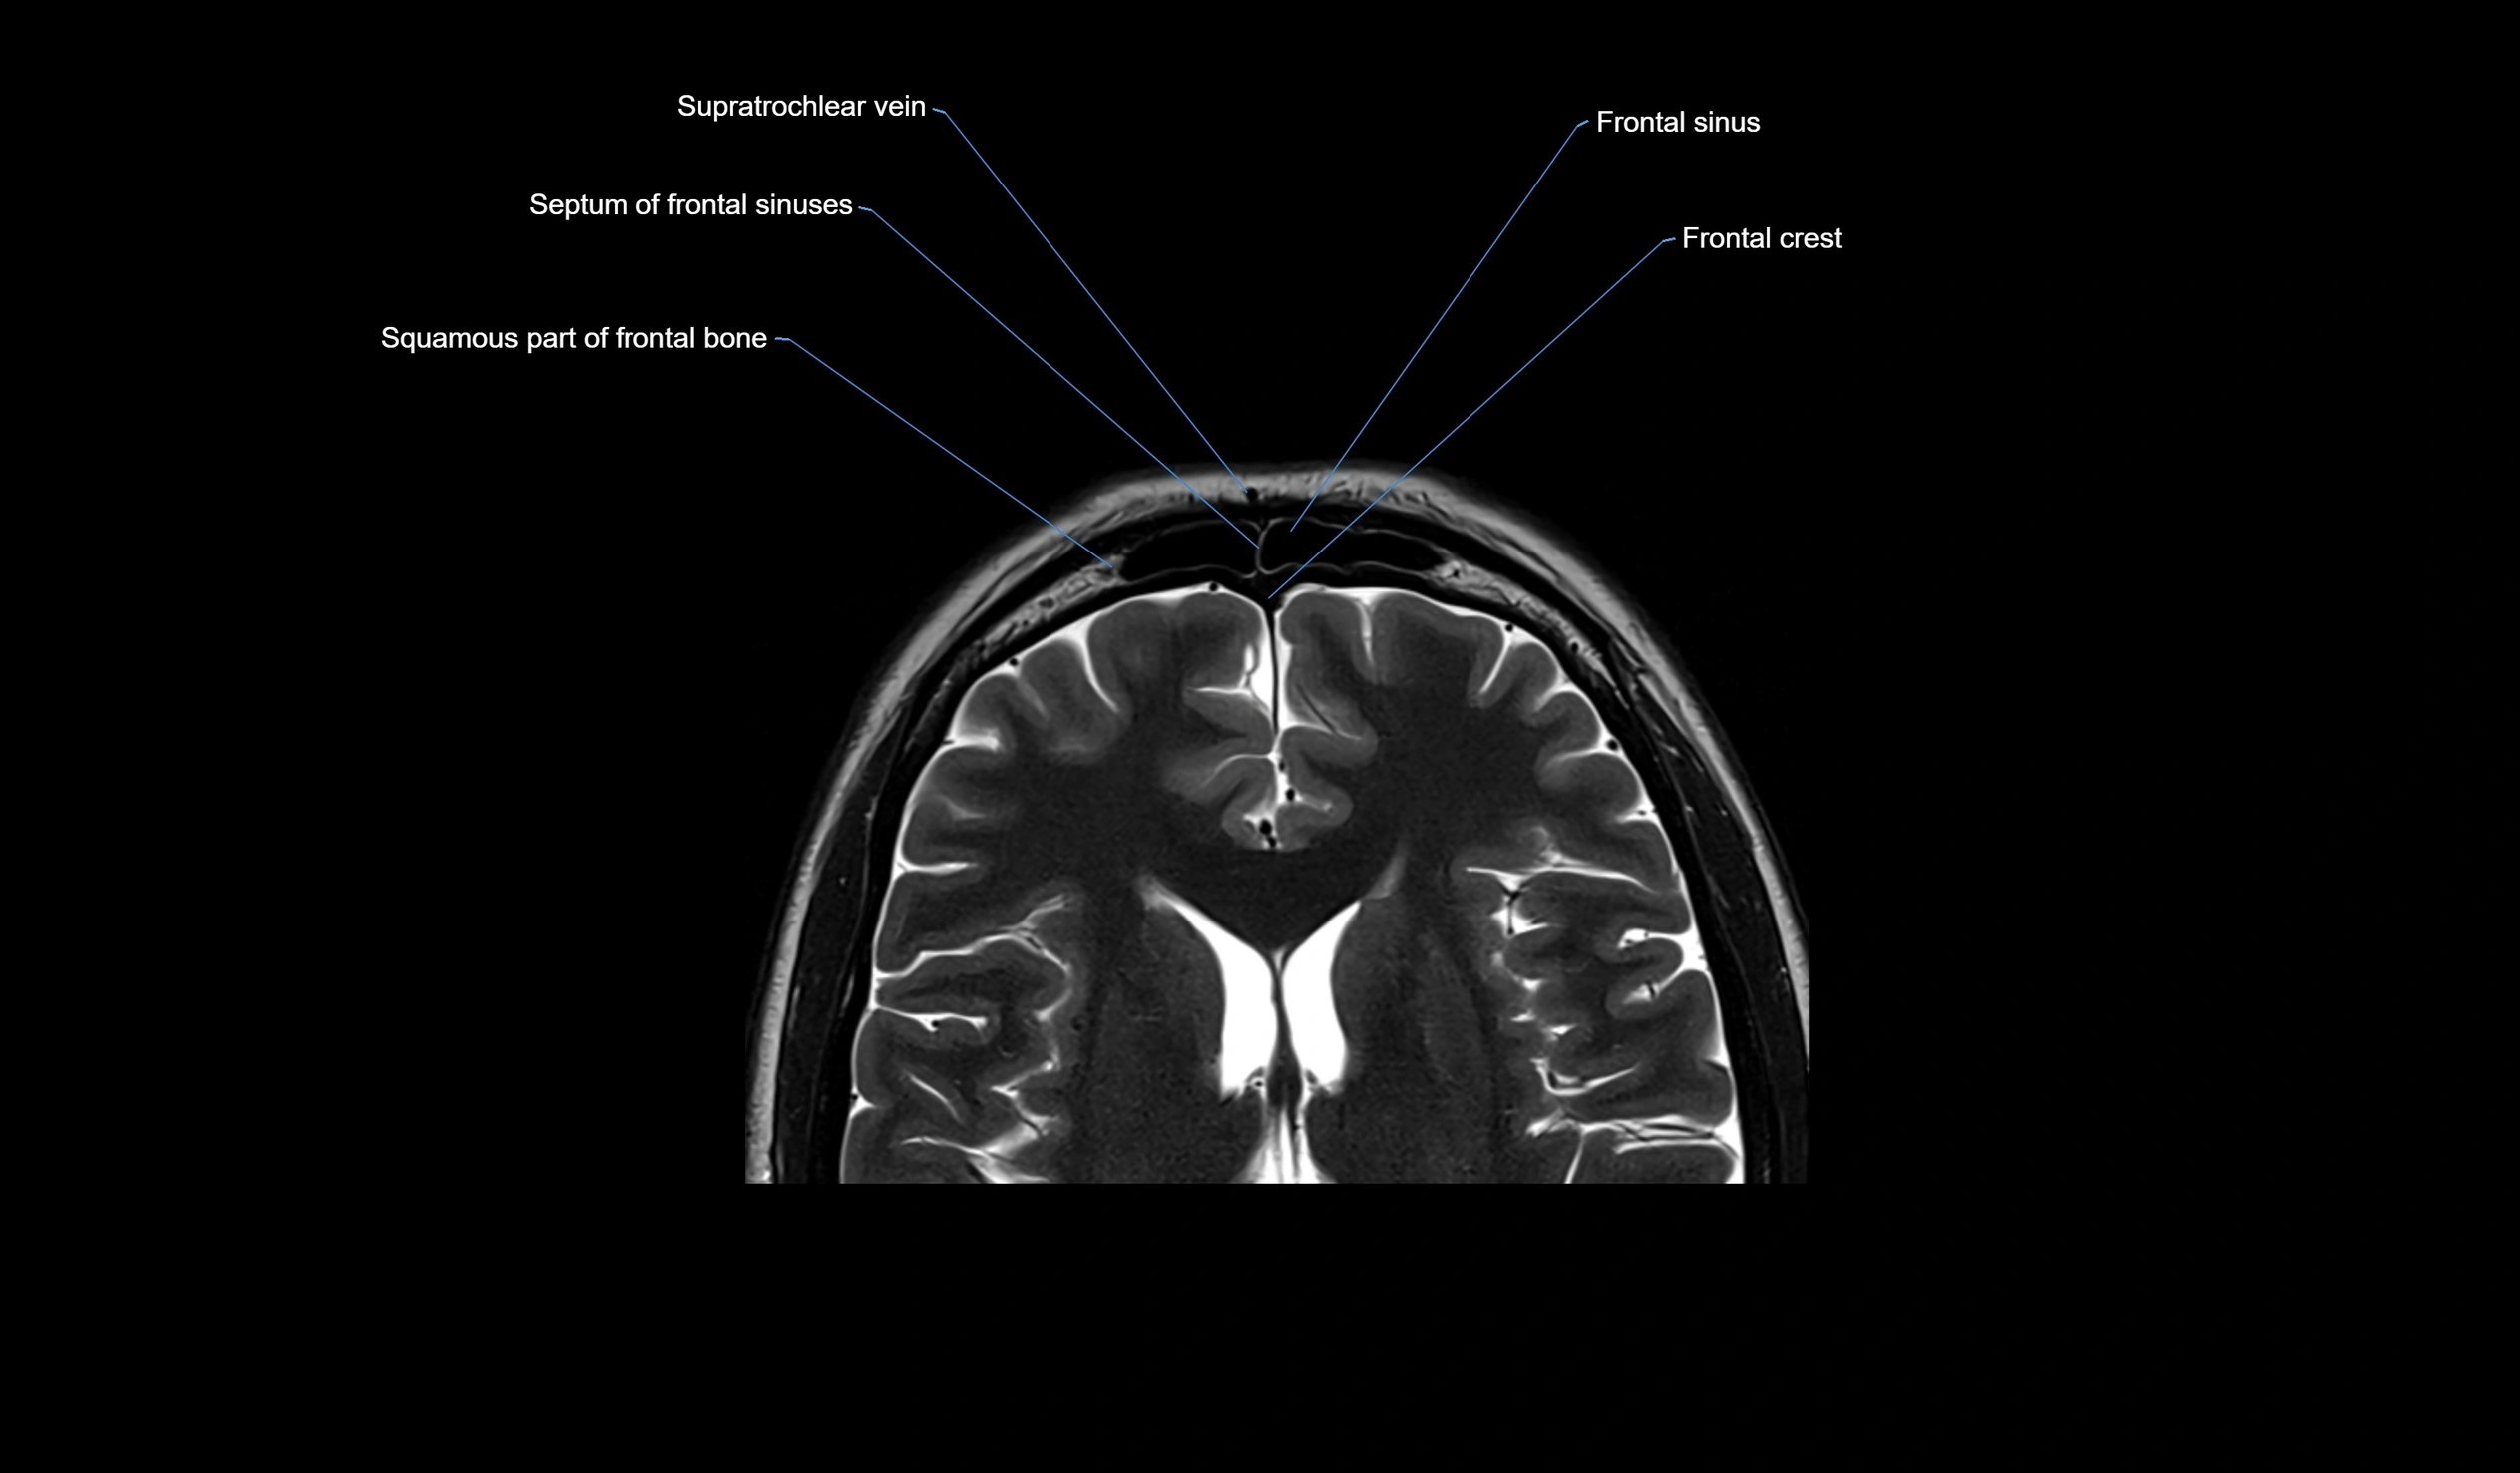

MRI images